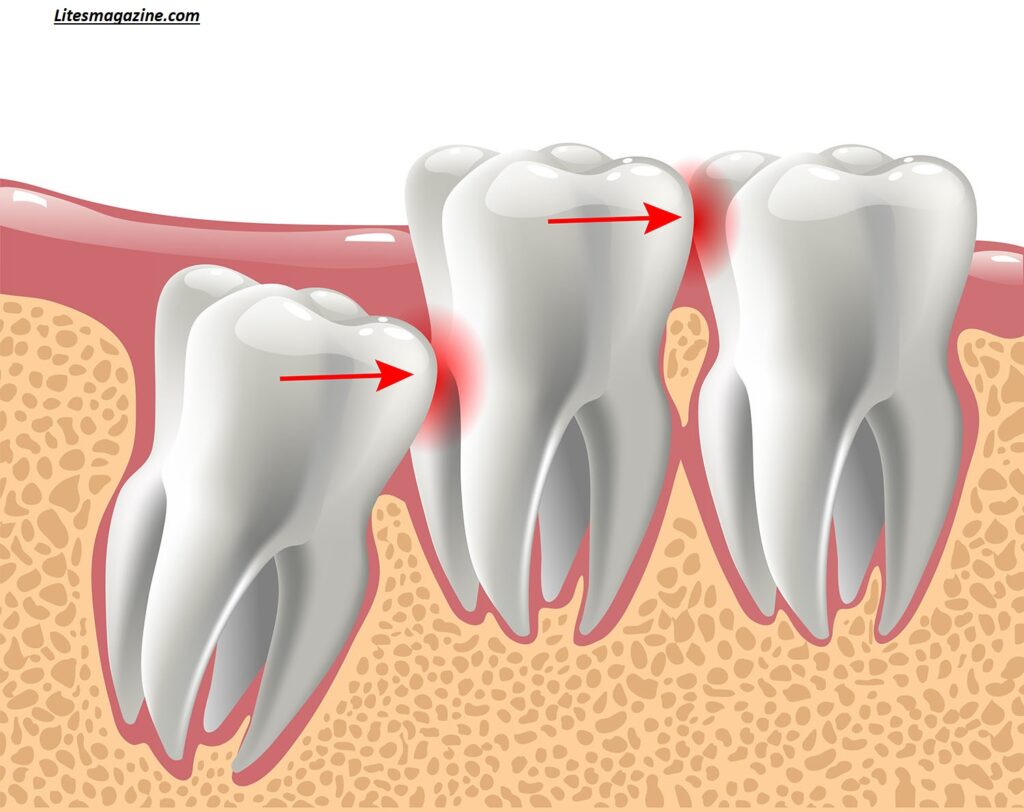

Today, many people don’t have enough space in their jaws for these late eruption teeth, leading to issues like impaction and misalignment.

Wisdom teeth can lead to several dental issues, especially when there isn’t enough space in the mouth. One of the most common problems is impaction, where the tooth gets stuck under the gums or grows at an angle.

Because these are late eruption teeth, they often struggle to find room to grow properly. This can cause pain, swelling, and even infection.

Another issue is crowding. When third molars push against existing teeth, they can disrupt alignment and undo previous orthodontic work.

Dentists usually recommend removal if there are signs of trouble. This includes pain, swelling, infection, or crowding. Impacted wisdom teeth are especially likely to require extraction because they can damage nearby teeth.